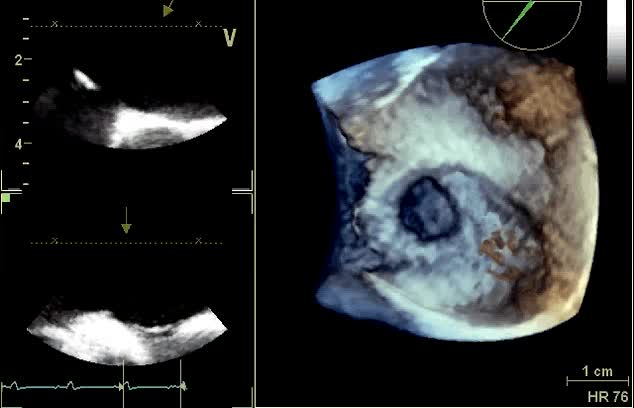

Cleft del lembo anteriore mitralico

Autore:

Andrea Barbieri